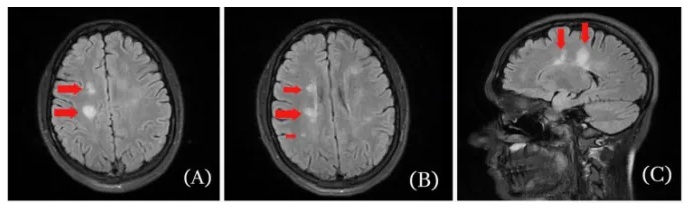

Sinusvenenthrombose

Sinusvenenthrombose 2 Röntgenfotos

Sinusvenenthrombose 2 Röntgenfotos [3]

Ein 80jähriger Mann wird in der Notaufnahme eines Krankenhauses vorstellig. Er leidet seit 2 Wochen unter schweren Kopfschmerzen, die mit Tinnitus und Sehstörungen einhergehen. Die Symptome haben sich einen Tag nach seiner ersten Behandlung mit der Gentherapie BNT162b2/Comirnaty von Pfizer/Biontech eingestellt. Schmerzmittel brachten keine Linderung, im Gegenteil, die Symptome wurden ergänzt durch psychologische Qual, Konzentrationsschwierigkeiten und Schlafstörung. Bei Aufnahme hatte der Mann einen erhöhten Blutdruck. Eine nähere Untersuchung ergab zudem eine Einschränkung seiner Sehfähigkeit, Schwäche in allen vier Gliedern und reduzierte Reflexe. Eine Kernspintomographie zeigt einen vollständig fehlenden Blutfluss in der transversen Sinusvenene und der linken Drosselvene, im Einklang mit der Diagnose einer zerebralen Sinusvenentrombose. Durch die sofort eingeleitete Behandlung mit Apixaban trat eine Besserung des Zustands des Mannes ein. Er konnte nach drei Monaten entlassen werden. Die Nachbehandlung dauerte bei Schriftlegung des Beitrags noch an.

Qureshi, Muhammad Imran Ahmad, Bilal Azam, Muhammad Aamir Waheed, and Afsheen Imran (2022). Venous sinus thrombosis after the first dose of Pfizer BioNTech vaccine. BMJ Case Reports CP 15(5): e247493.